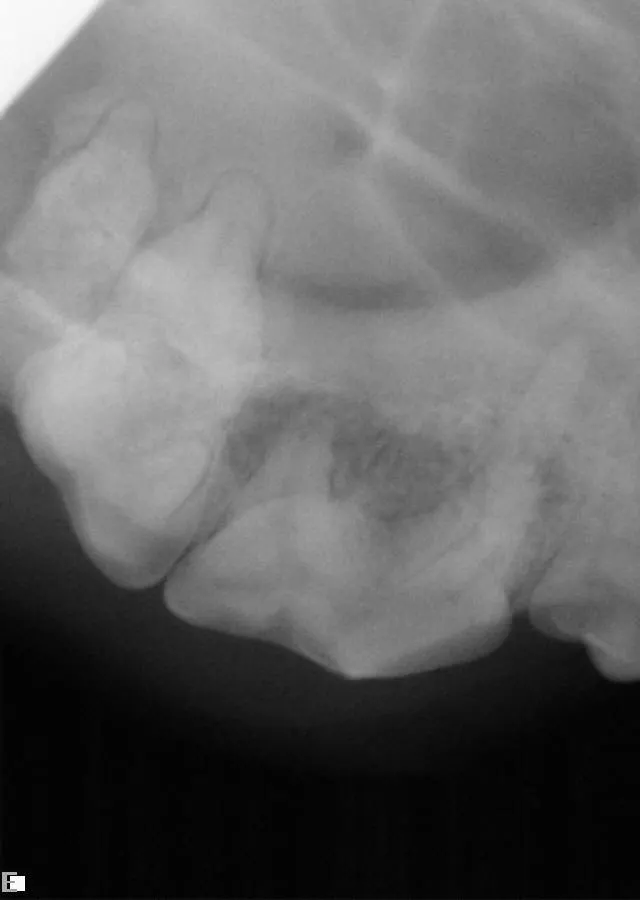

A maxillary extraoral draining tract rostral to the eye is most commonly associated with chronic infection (periodontal or endodontic) of a maxillary premolar or molar tooth (Figure 6). In brachycephalic breeds, it might even be the canine tooth. Dental disease is subgingival, and both periodontal and endodontic infections can result in maxillary draining tracts. There may be associated bone proliferation or reaction, and the region may be firm on palpation. Dental disease should be the top differential for these lesions before dermatologic conditions, ophthalmologic conditions, or tumors are considered. The infected tooth can be identified with general anesthesia, oral examination, periodontal probing, and intraoral radiographs of the maxillary regional dentition on the ipsilateral side of the draining tract (Figures 7 and 8) with similar radiographs of the contralateral side for comparison. Surgical extraction of the infected tooth or teeth is often necessary. The carnassial tooth is not always at fault; therefore, intraoral radiographs are needed to diagnose the infected tooth, which could be any of the ipsilateral dentition (eg, first maxillary molar).